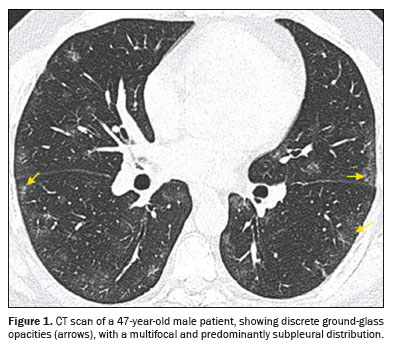

Ground-glass opacity (Figure 1) is characterized by increased lung density that does not obscure the internal vascular structures and should be differentiated from consolidation, in which the vessels are not visible. When accompanied by thickening of the interlobular septa, it forms what is known as the crazypaving pattern, which was not observed in our study sample. An air bronchogram (Figure 2) is defined as visible aerated bronchi within areas of consolidation or atelectasis. The interlobular septa, which delimit the secondary pulmonary lobule, are composed of connective tissue, pulmonary veins, and lymphatic vessels; the septa can present smooth, irregular, or nodular thickening in conditions such as edema, inflammation, fibrosis, and neoplasia. A parenchymal band (Figure 3) is an elongated linear opacity, commonly peripheral and accompanied by fibrosis or interstitial thickening, frequently in contact with the pleura, which can present thickening and retraction

Most (76.3%) of the examinations showed multifocal involvement, with diffuse involvement being seen in the remaining nine examinations (23.7%). The distribution of lung involvement, in terms of location, was subpleural in 71% of the cases (Figure 1), being peribronchial or diffuse in 29%. As detailed in Table 2, the extent of lung involvement was classified as follows: mild (up to 25%), moderate (25–50%), or severe (over 50%).